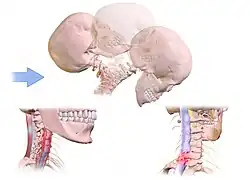

- Chronic whiplash injury associated pain

Chronic secondary headache or orofacial pain is a result of an underlying disorder.[24] Chronic secondary headache or orofacial pain can be caused by ischemic stroke, nontraumatic intracranial hemorrhage, arteritis, unruptured vascular malformation, pituitary apoplexy, genetic vasculopathy, increased cerebrospinal fluid pressure, Chiari malformation type I, intracranial neoplasms, epileptic seizure, substance withdrawal,[24] bacterial meningitis, meningoencephalitis, viral meningitis or encephalitis, brain abscess, intracranial fungal or other parasitic infections, hypoxia, hypercapnia, dialysis, arterial hypertension, and hypothyroidism.[25]

- Chronic headache or orofacial pain associated with cranial or cervical vascular disorder

- Chronic headache or orofacial pain attributed to trauma or injury to the head and/or neck